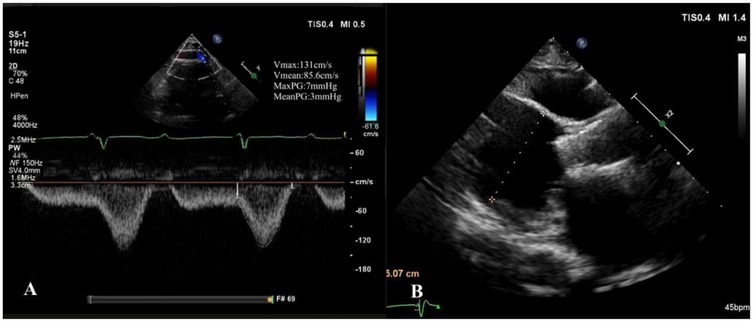

Our hospital admitted a 53-year-old female patient who presented with a chief complaint of “intermittent chest discomfort for 4 years, with exacerbation over the past week”. In 2020, the patient experienced chest discomfort after physical activity, accompanied by shortness of breath and palpitations. She was subsequently diagnosed with ischemic cardiomyopathy and heart failure at a local hospital. Despite receiving guideline-directed medical therapy (GDMT), her condition persisted with recurrent symptoms and progressive worsening. Consequently, on May 8, 2021, she was initiated on continuous renal replacement therapy, utilizing continuous venous-venous hemofiltration. On May 25, 2022, the patient underwent implantation of a LVAD (HeartCon model) in conjunction with coronary artery bypass grafting (CABG). Postoperatively, her symptoms improved significantly, allowing for discharge. However, in June 2024, the patient presented again with chest discomfort and was admitted to our hospital for further evaluation. At admission, the parameters of LVAD were as follows: pump speed 2,300 rpm, power 5.10 W, and flow rate 7.85 L/min. Laboratory tests revealed an elevated N-terminal pro-B-type natriuretic peptide (NT-proBNP) level of 4,864 pg/ml. Echocardiography indicated moderate to severe regurgitation of the aortic valve (Figure 1).

Figure 1

Moderate to severe regurgitation of the aortic valve.

At the 1-month follow-up, the patient's symptoms had markedly improved (NYHA functional class II). Transthoracic echocardiography demonstrated normal morphology and function of the prosthetic valve, with no evidence of late prosthesis migration, and spectral Doppler imaging revealed no regurgitation (Figure 5). LVAD parameters remained stable throughout the follow-up period (pump speed 2,200–2,300 rpm, flow approximately 2.5 L/min).

Figure 5

One-month postoperative echocardiographic follow-up. (A) Spectral Doppler showing no evidence of aortic regurgitation; (B) long-axis view demonstrating no late prosthetic valve migration.